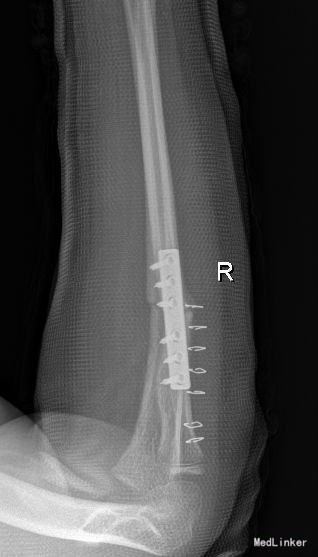

西医诊断:右尺桡骨骨折 治疗:全麻下行“右尺骨骨折切复内固定术”

后给予石膏外固定,抗菌素预防感染,促进愈合等药物治疗,适时换药、拆线并相关理疗。